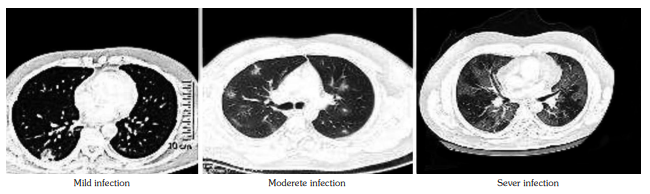

The patients that recovered from COVID-19 (n=31) were subjected to serum vitamin D level measurement after eight weeks from recovery. Eleven patients who had normal levels at the time of infection remained having normal vitamin D levels eight weeks after recovery, while in 16 of 20 patients who had low baseline vitamin D levels, the levels returned to normal range eight weeks after recovery. Fatigue was one of commonest manifestation of both SLE and post-COVID-19. Fatigue was evaluated in 31 patients that recovered from infection; four of 11 (36.3%) patients with normal baseline vitamin D levels and 12 of 20 (60%) patients with low baseline vitamin D levels had persistent fatigue (Figure 2).